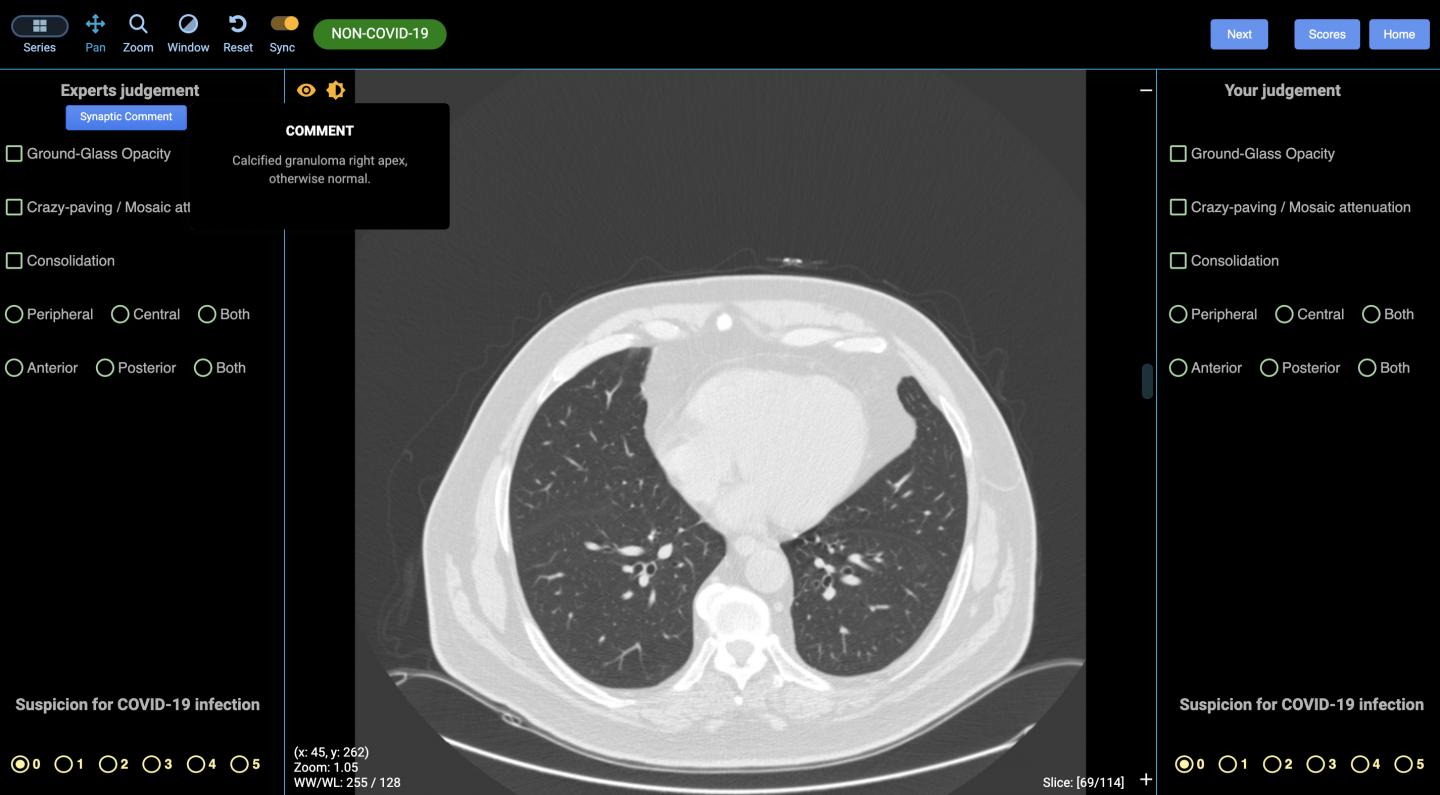

The cloud-based life-saving technology, developed by Australian-based radiation and imaging experts DetectED-X, will help doctors and radiologists diagnose cases faster and more accurately. Computed tomography (CT) lung scans, which produce cross-sectional images using X-rays and computers, have typically been used after swabs are taken, to identify the extent and location of the disease; the CT scans produce images within minutes and are also able to diagnose COVID-19 in the very early stages that escape detection with the nucleic acid tests.

DetectED-X's approach, which includes algorithms to improve radiologist skills and identifying where errors were made on images in the online training sessions, has been shown to improve results significantly*. The CovED platform uses CT images from cases with appearances of COVID-19 arising from Australia (Queensland, Victoria, NSW) and collaborators in Europe.

Through CovED, individual clinicians can assess their performance on images on screen, and receive immediate feedback including performance scores used in the industry. The image files personalised for each clinician are instantly returned showing any errors in their virtual diagnosis and the difficulty level is increased over time.

Radiologic detection is the front-line tool for identifying early lung changes such as acute presentations such as bilateral ground-glass opacities and consolidative pulmonary opacities (a type of pneumonia) , with these progressing to consolidation, greater total lung involvement, linear opacities, crazy-paving patterns and the reverse halo sign at later stages . High resolution computed tomography (CT) which outperforms plain chest X-rays , is sensitive and specific for COVID-19 infection, even at early stages of concentrated viruses in a sample, when viral titres are equivocal. It is routine, involving low radiation dose and can be acquired rapidly.

While CT can display the signs, the subtle lung appearances representing early stage disease remain challenging for non-specialized reporters resulting in significant diagnostic errors: the sensitivity of CT for detection of lung lesions can be as low as 70 percent for experienced and 51 percent for less experienced radiologists . For HRCT to play a useful role in facilitating early COVID-19 diagnosis at the scale necessary, rapid improvements in reporting accuracy are needed.